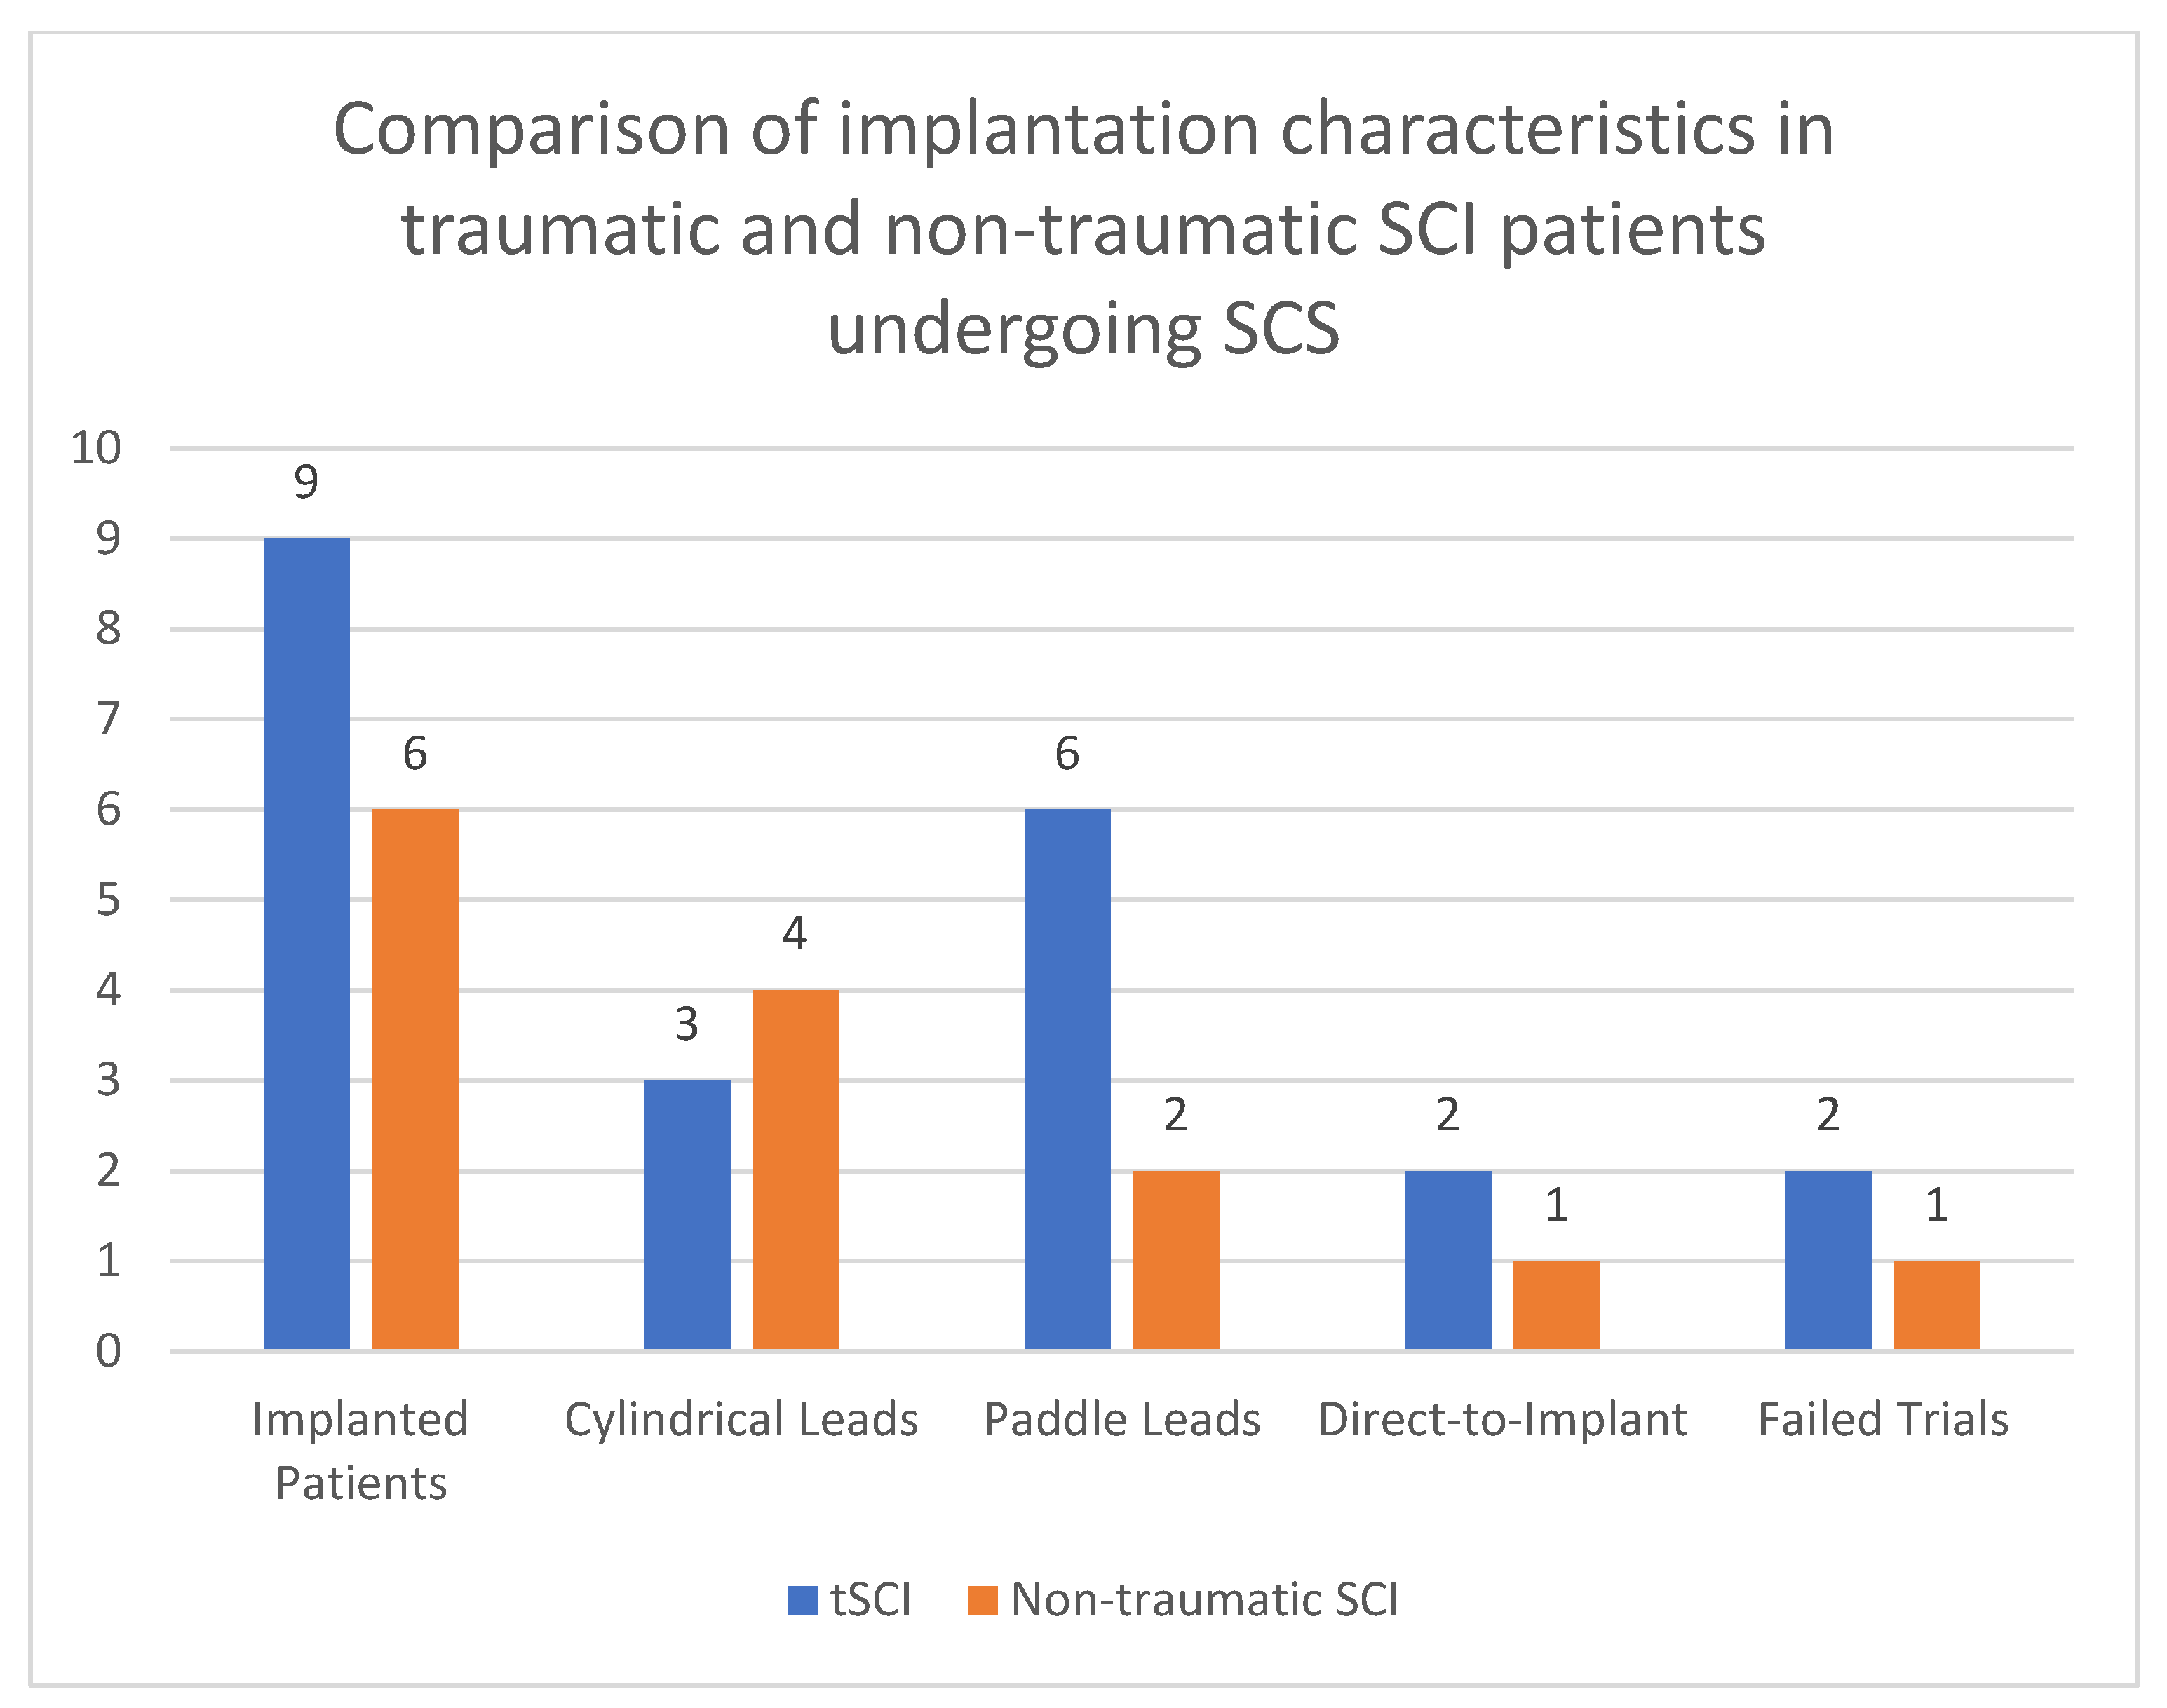

3. Results

3.1. Demographic and Clinical Data